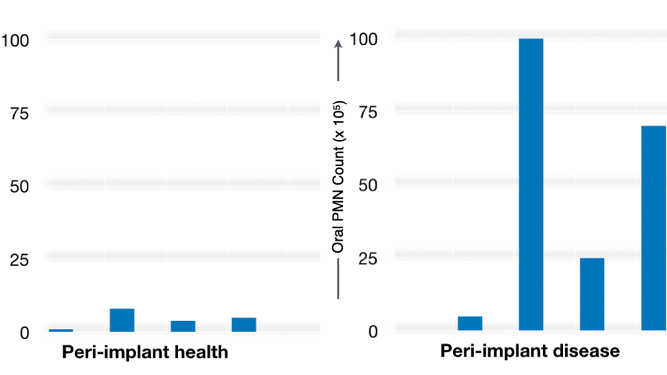

Researchers found that scaffolds loaded with strontium at any concentration stimulated wound healing A team of University at Buffalo researchers has developed a new strontium-loaded scaffold that can be personalized to fit any size dental implant and could help improve healing and tissue attachment in patients. The success of dental implants is dependent on the … Read more